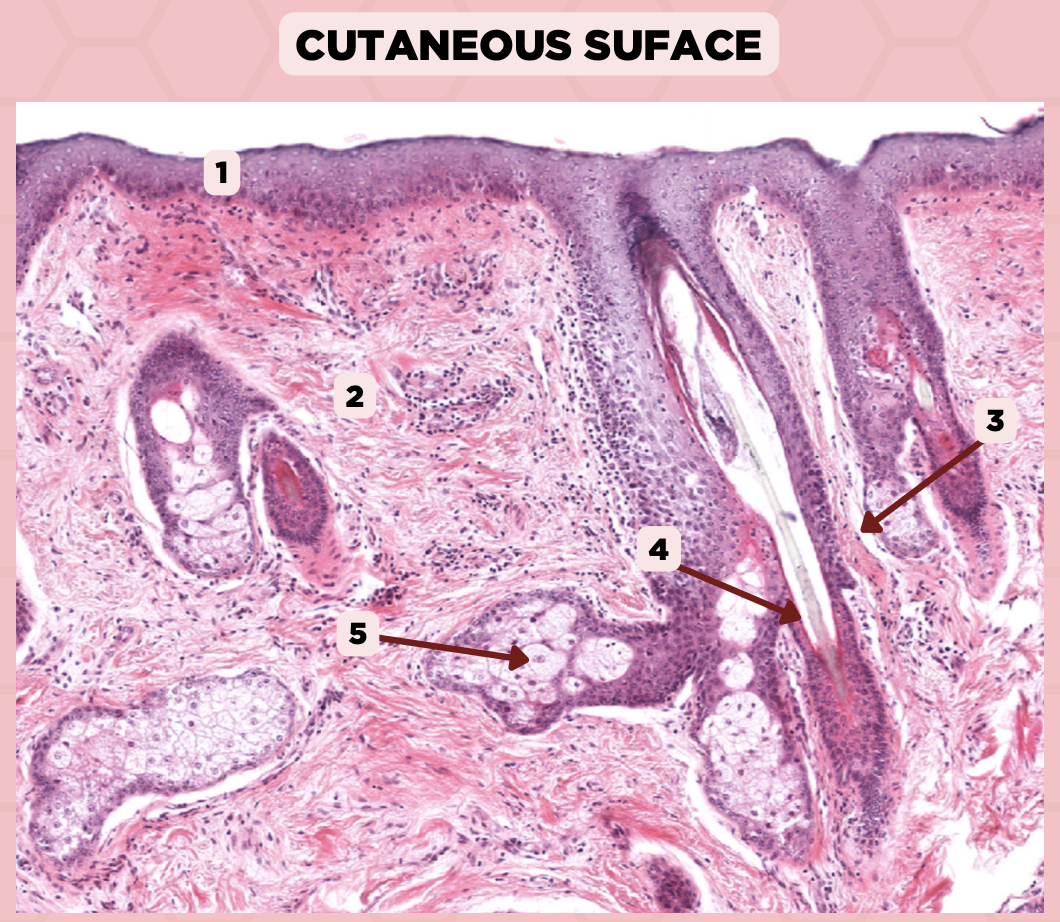

Lip

What specimen is being showed in the picture?

Epidermis

Identify the structure labeled as 1.

Dermis

Identify the structure labeled as 2.

Arrector Pilli Muscle

Identify the structure labeled as 3.

Hair Follicle

Identify the structure labeled as 4.

Sebaceous Glands

Identify the structure labeled as 5.

Lip

What is the specimen showed in the picture?

Epidermis

Identify the structure labeled as 1.

Dermis

Identify the structure labeled as 2.

Arrector Pilli Muscle

Identify the structure labeled as 3.

Hair Follicle

Identify the structure labeled as 4.

Sebaceous Glands

Identify the structure labeled as 5.